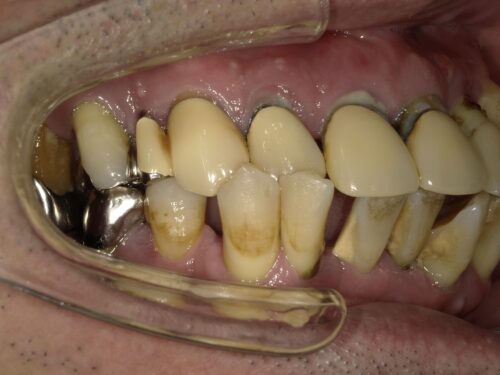

奥歯も残っていますが歯周病で根元まで見えてしまっていたり、

歯の向きが変わってしまっているところもあります。

下の大臼歯とよばれる奥歯はもうありませんでした。

このままだと傾いた前歯のあたりで噛むことが続き、

より歯周病の進行を早めてしまいます。